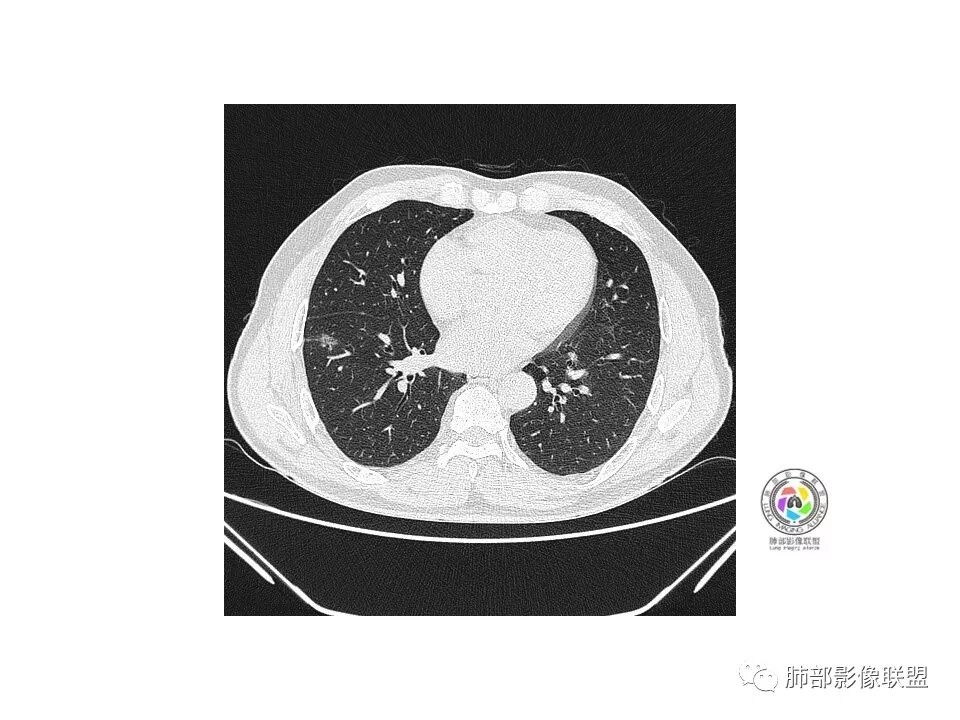

右肺下叶见边界清晰混合磨玻璃密度影,目测内见实性结节小于5mm,有浅分叶,前缘小叶间隔阻挡,月牙铲?胸膜牵拉,老年患者,MIA可能,鉴别炎性病变,抗炎后复查

患者老年男性,以咳嗽 、咳痰3天就诊,胸CT:右肺下叶前基底段mGGO,内可见血管形态改变,细支气管扩张,病灶边界清,边缘可见月牙铲。考虑恶性,腺癌?但建议先抗炎治疗后复查

右肺下叶混合磨玻璃结节,边缘清晰,浅分叶,月牙铲,胸膜牵拉,血管进入,考虑MIA可能,鉴别炎性病变

患者老年男性,咳嗽  咳痰3天就诊。胸部CT:右肺下叶前基底段混合磨玻璃结节,边缘清楚,可见毛刺、胸膜牵拉、血管集束、月牙铲征象。综合考虑微浸润腺癌可能大。

右肺下叶前基底段混合磨玻璃结节,边界清,浅分叶,胸膜牵拉,月牙铲,血管进入,考虑:微浸润腺癌可能性大,抗炎后复查。

老年男性,咳嗽、咳痰3天。胸部CT:右肺下叶前基底段mGGN,边缘清楚,内可见不规则实性成分,病灶可见空泡、毛刺、胸膜牵拉、血管集束征象。考虑MIA可能大,抗炎2W后复查。

老年男性,右下肺前基底段混合GGN,边缘清晰,月牙铲,叶间胸膜牵拉,有轻度收缩力。结合病史抗炎2-3周后复查,消失考虑炎症,变化不大为腺癌。本例总体支持腺癌

老年男性,咳嗽3天,右肺下叶前基底段混合磨玻璃结节,形态不规整,相邻胸膜凹陷,可见血管影,考虑腺癌可能性大,不除外炎症可能,建议抗炎1~2周,1个月复查胸部CT。

老年男性,右肺下叶前基底段斜裂旁可见单个混合型磨玻璃结节mGGN,边缘清,内部结构紊乱,进入的血管增粗,支气管关系不好判断,斜裂侧可见牵拉,常规考虑微侵腺癌MIA,建议先抗炎后复查及手术干预。

老年男性,咳嗽咳痰3天。MGGN,边缘见月牙铲、胸膜牵拉,血管移动联通?冠状位隐约可见支气管穿行,考虑MIA,重建冠位可见结节比较靠近叶裂,可积极手术处理。

患者老年男性,右下肺前基底段靠近胸膜侧可见一个mGGO结节,边缘清淅,可见分叶征及月牙铲,小结节病灶胸膜牵拉明显,首先考虑MIA可能性大。

右肺下叶mGGO,边缘清晰,浅分叶,内血管影增粗,见点状实性成分,小支气管牵拉扩张,考虑MIA,建议抗炎后复查。

右肺下叶前基底段mGGN,边界清晰,内部结构杂乱,见网格空泡感,月牙铲,浅分叶及胸膜牵拉,倾向MIA。